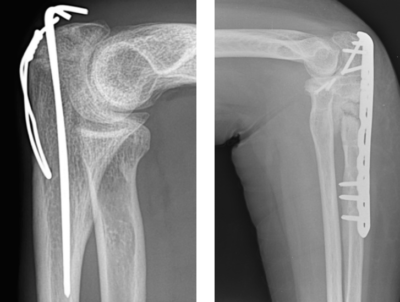

Ostéosynthèse par brochage-haubanage ou par plaque

Pour les fractures instables ou déplacées, même si les os sont repositionnés et qu’un plâtre est mis en place ensuite, les fragments osseux auront tendance à re-bouger secondairement ou à adopter une mauvaise position avant de consolider. Ces fractures nécessitent donc une intervention chirurgicale afin de rétablir et maintenir l’alignement des os en les fixant avec du matériel (plaque ou broches).

L’intervention se déroule au bloc opératoire, sous anesthésie loco-régionale (seul le bras est endormi), en ambulatoire (vous entrez et sortez de l’hôpital le même jour que votre intervention). La cicatrice réalisée sur le coude mesurera environ 7 à 15 centimètres.